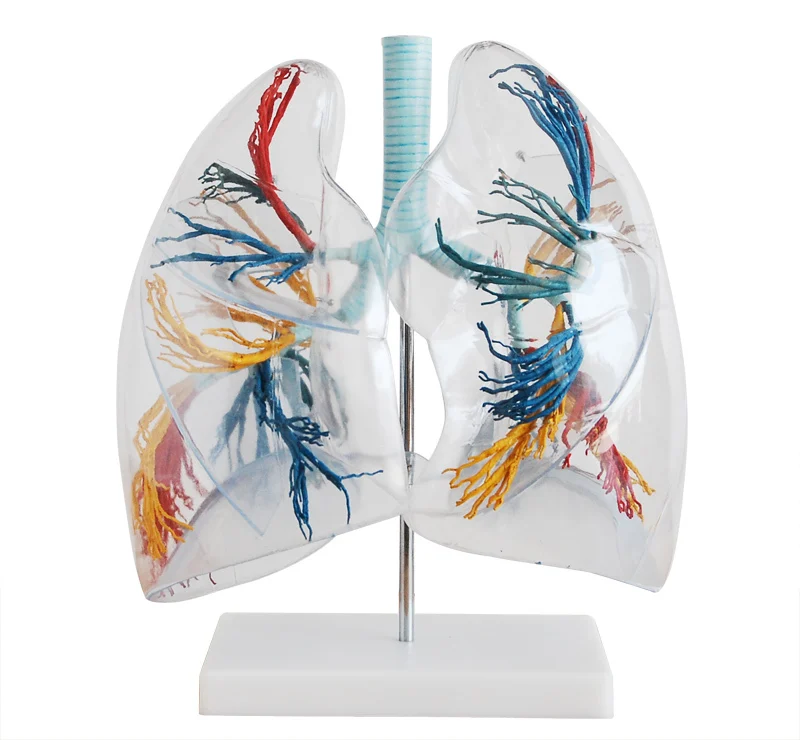

Анатомические изображения сегментов легких различных животных

Раздел: Другие животные